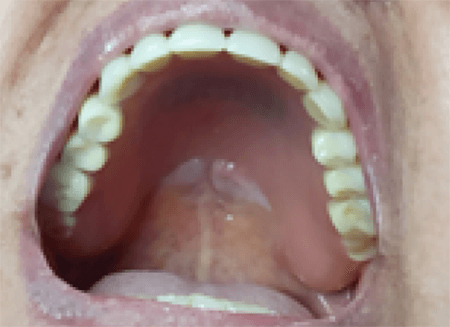

Al examen intraoral, se observa que la paciente es portadora de prótesis completa bimaxilar y se identifican, en el tercio posterior del paladar duro a ambos lados de la línea media, dos lesiones de aspecto tumoral, de forma ahusada y dimensiones de 3 x 1.5 cm, recubiertas por mucosa de apariencia normal, de color rosa pálido, con límites netos, base no indurada, consistencia blanda e indoloras a la palpación. Fig. 1.

Figura 1. Imagen clínica del maxilar superior y dos lesiones de aspecto tumoral ubicadas en tercio posterior del paladar duro a ambos lados de la línea media.

Al evaluar la relación de la lesión con la prótesis, se evidencia un estrecho contacto entre el aparato protésico y el borde anterior de una de las lesiónes. Fig. 2.